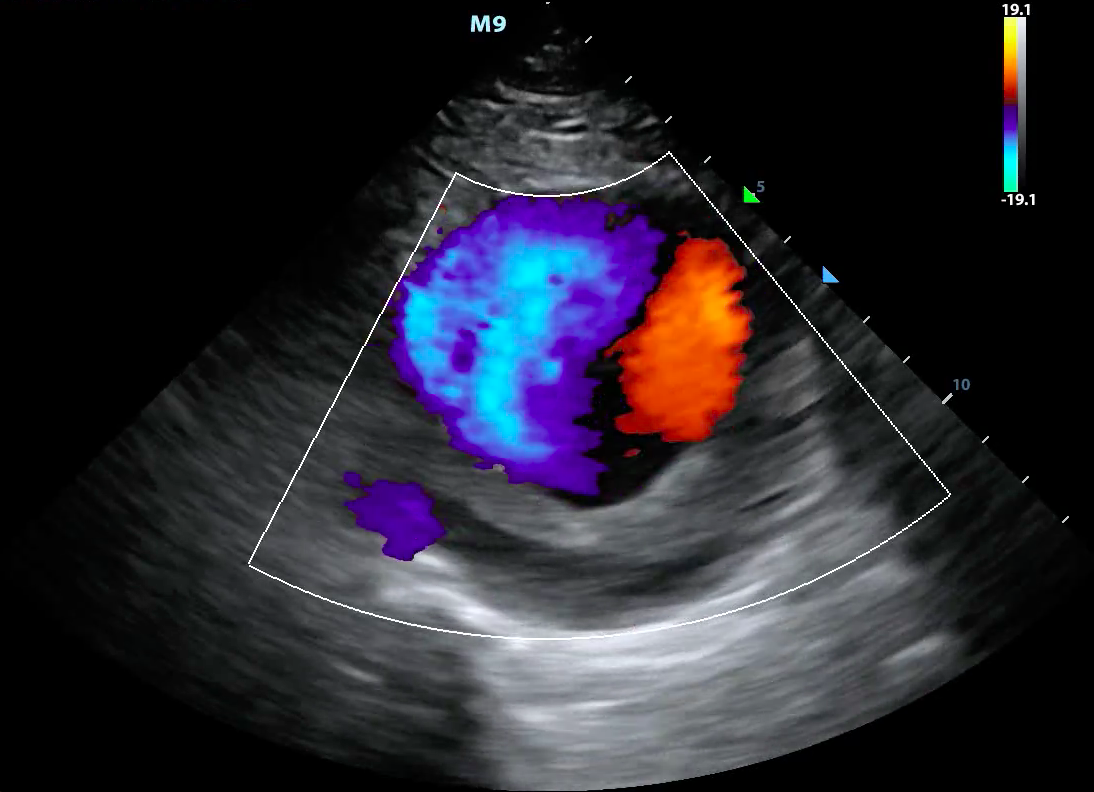

- Color Doppler ultrasound is also called color-flow ultrasound.

- It is used to show blood flow or tissue motion in a selected two-dimensional area

- Direction and velocity of tissue motion and blood flow are color coded and superimposed on the corresponding B-mode image (Figure 3, Video 2)

- Typically, red depicts movement towards the transducer, while blue depicts movement away from the transducer

- Figure 3. Color doppler showing turbulent blood flow in a large abdominal aortic aneurysm

Video 2. Color doppler showing turbulent blood flow in a large abdominal aortic aneurysm